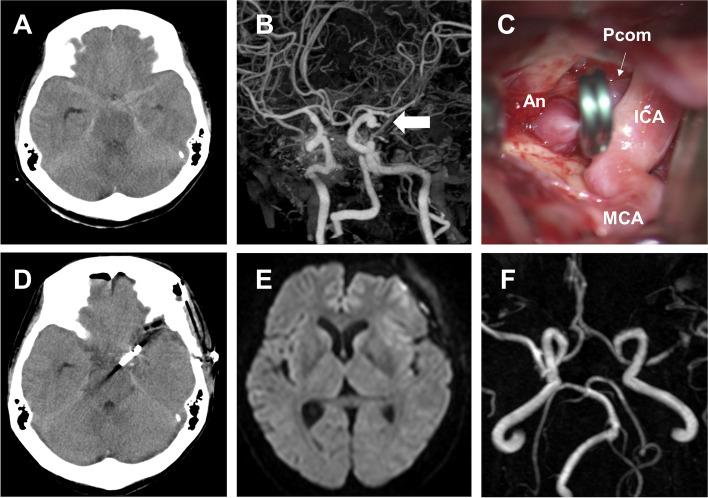

The patient was a 52-year-old woman. While bathing at home, the patient experienced a sudden disturbance of consciousness and was brought to our hospital. The main physical findings upon admittance were Glasgow Coma Scale score of E1V2M4, elevated blood pressure (208/145 mmHg), and tachycardia with atrial fibrillation (180 bpm) along with body temperature of 36.1 °C. Brain computed tomography revealed subarachnoid hemorrhage associated with a ruptured aneurysm of the posterior communicating artery branching from the left internal carotid artery, and aneurysm clipping was performed. Blood tests upon admission revealed high levels of free T3 and free T4 and low levels of thyroid-stimulating hormone. Upon determining that the patient had hyperthyroidism, thiamazole was administered. However, due to continuous impaired consciousness, fever, and persistence of tachycardia, the patient was diagnosed with thyroid storm. Oral potassium iodide and hydrocortisone were added to the treatment. The treatment was successful as the patient's symptoms improved, and she became lucid. In this case, we believe that in the presence of untreated hyperthyroidism, the onset of subarachnoid hemorrhage induced thyroid storm. Tachycardia of 130 bpm or higher, which is the diagnostic criterion for thyroid storm, rarely occurs with subarachnoid hemorrhage. Therefore, we believe it is an important factor for recognizing the presence of the thyroid storm. In this case, clipping surgery was prioritized which resulted in a favorable outcome. However, it is possible that invasive surgery may have exacerbated thyroid storm, suggesting that treatment should be tailored as per patient's condition.

患者为一名52岁女性。在家中洗澡时,患者突然意识障碍,被送至我院。入院时的主要体格检查结果为格拉斯哥昏迷量表评分为E1V2M4,血压升高(208/145 mmHg),伴有心房颤动的心动过速(180次/分钟),体温为36.1℃。脑部计算机断层扫描显示蛛网膜下腔出血,与发自左颈内动脉的后交通动脉的动脉瘤破裂有关,并进行了动脉瘤夹闭术。入院时的血液检查显示游离T3和游离T4水平升高,促甲状腺激素水平降低。在确定患者患有甲状腺功能亢进症后,给予了甲巯咪唑治疗。然而,由于患者意识持续障碍、发热且心动过速持续存在,患者被诊断为甲状腺危象。治疗中加用了口服碘化钾和氢化可的松。随着患者症状改善且意识清醒,治疗取得成功。在本病例中,我们认为在存在未经治疗的甲状腺功能亢进症的情况下,蛛网膜下腔出血的发作诱发了甲状腺危象。甲状腺危象的诊断标准为心率130次/分钟或更高,蛛网膜下腔出血很少出现这种情况。因此,我们认为这是识别甲状腺危象存在的一个重要因素。在本病例中,优先进行了夹闭手术,结果良好。然而,侵入性手术可能会加重甲状腺危象,提示应根据患者情况制定个体化治疗方案。